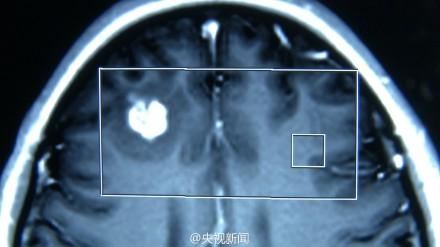

当晚在急救车上,她连着抽搐了两次。在苏州的一家医院进行核磁共振等检查后,医生在她的脑部右侧额叶发现了一个病灶。医生怀疑是胶质瘤,说是只有开颅探查后才能确定。

8月14日,小静被推进手术室,外科杨坤医生从她脑中取出一条乳白色的东西,长达3厘米。

“这是绦虫的囊虫,成虫能长到2到4米,但是主要寄生在肠道里,而囊虫可以随着血液在四处游走。”杨坤医生分析说,患者可能是一开始误食了猪肉中的猪肉绦虫虫卵,经消化道进入肠壁再进入肠系膜静脉,最后经血液循环将虫卵送到大脑,引起一系列的症状。这种疾病也叫“脑囊虫病”,患病如不及时治疗,脑组织及大脑中枢则易受损,进而引起头疼、无力、肢体运动障碍症状,严重的会引发癫痫,视物不清甚至死亡。